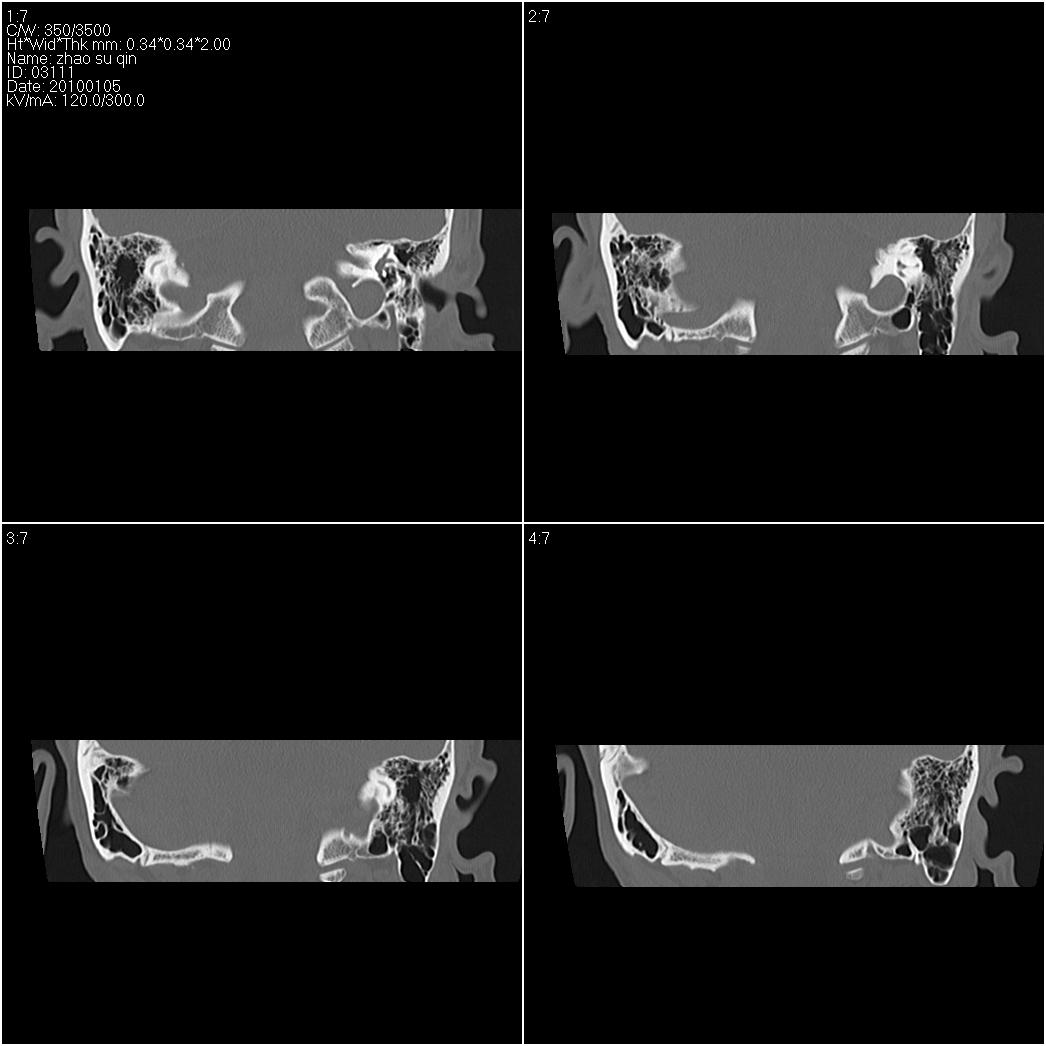

标题: CT24015:一个头部外伤患者进行鉴定,除了左侧筛板骨折,哪 [打印本页]

标题: CT24015:一个头部外伤患者进行鉴定,除了左侧筛板骨折,哪

1)左侧筛板骨折。2)双侧筛窦炎症(或积血)。

请明示骨折部位。